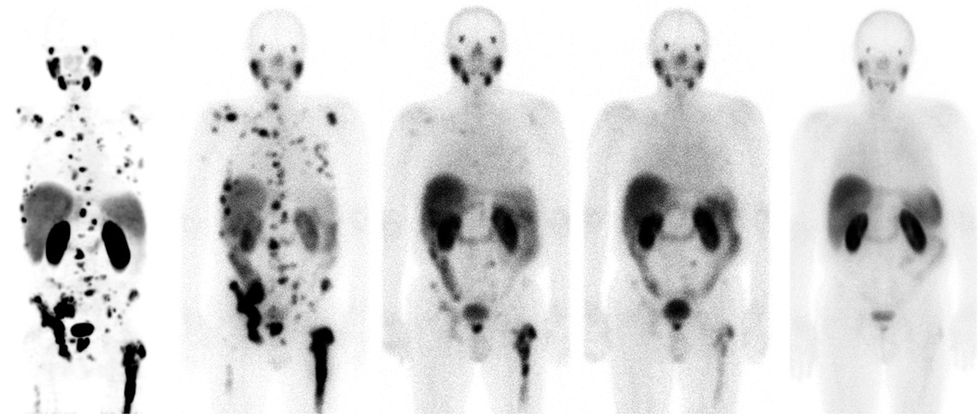

El médico dió a conocer el caso de un hombre alemán de 62 años, el cual presentó cáncer de próstata y una diseminación masiva con metástasis en los huesos.

Al paciente le fue aplicado un tratamiento experimental basado en teragnosis en la Clínica Central de Bad Berka (Alemania), posteriormente 8 meses después de haber recibido el tratamiento, no se observaron señales de cáncer, volviendo a retomar su vida cotidiana (regresó a trabajar y a hacer deporte), 3 1/2 años después seguía sin mostrar ningún tipo de sintomatología de cáncer.

Para poder llevar a cabo el correcto diagnóstico, la molécula afin al PSMA debe ser unida a un elemento químico radiactivo, en este caso el galio-68, el cual tiene propiedades que suelen brillar en las exploraciones realizadas mediante las tomografías por emisión de positrones (PET).

Para el tratamiento que requiere cada paciente, la misma molécula utilizada debe ser unida a otro elemento químico, el lutecio-177, elemento que a su vez suele emitir radiación local, logrando anular y matar a las células cancerígenas.